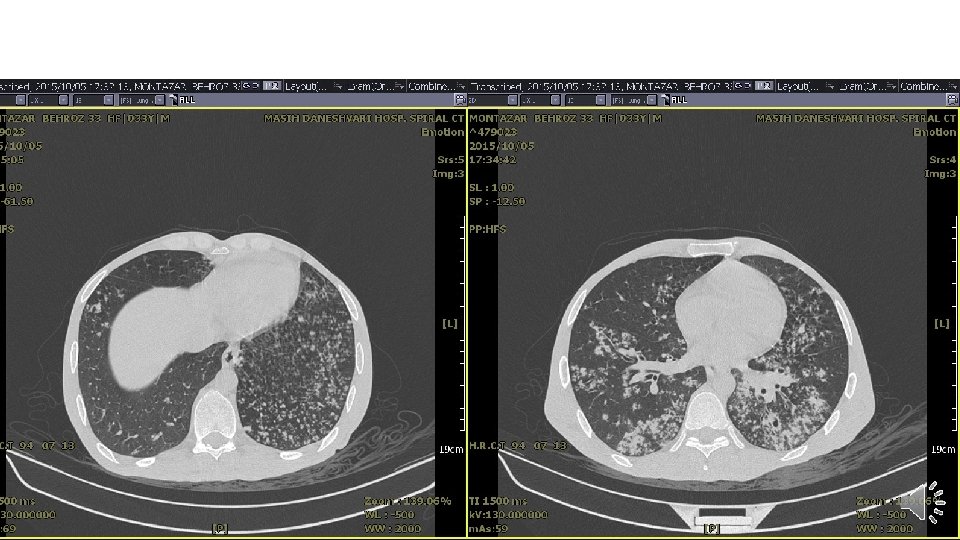

Lung CT scan

Diagnosis and management • Sputum smear for AFB: 3+ • Anti TB was initiated: FDC (HRZE) 3/d • ART (Vonavir) & Cotrimoxazole was continued. Is It enough?